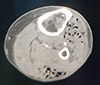

Se solicita exploración de MMII por descompensación grave de paciente en UCI, cuadro séptico y piel oscurecida . En la exploración ecográfica se visualiza aire en el cayado de la safena y en la pierna (sin poder establecer el plano exacto). La exploración con TAC muestra burbujas de aire en tejidos profundos, musculares, en zona tibial tanto anterior como posterior.